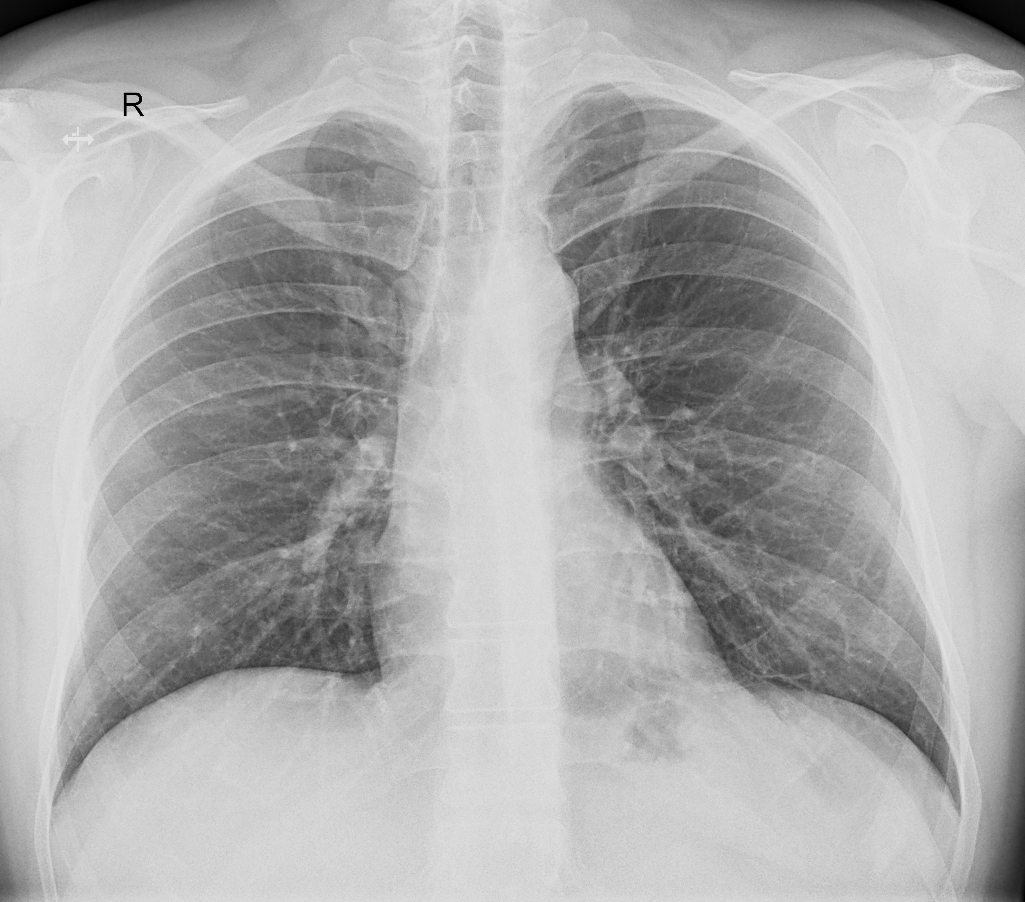

Opacitate micronodulara posibil sechelara apical stanga.

Banda opaca liniara - subclavicular stanga.

Trama vasculointerstitiala usor accentuata infrahilar stanga.

Contur cardiomediastinal normal.